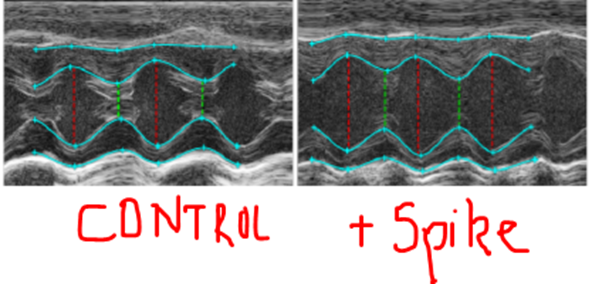

Dilatation des cellules cardiaques/cardiomyocytes :

Remodelage hypertrophique du cœur : à gauche - cœur normal ; à droite cœur gonflé suite à l'effet agressif de la Spike

L'hypertrophie du cœur est permanente = la forme du cœur change et ses cellules ne dégonflent pas pour revenir à leur état « normal » ! Ce sont des dommages cardiaques permanents avec des risques pouvant aller de la mort en passant par la nécessité de greffe ou à long terme des complications cardiaques chroniques. Il n'y a rien de bénin ou de « soignable » après une myocardite. On ne fait que cacher les dommages comme mettre du vernis sur des ongles sales.